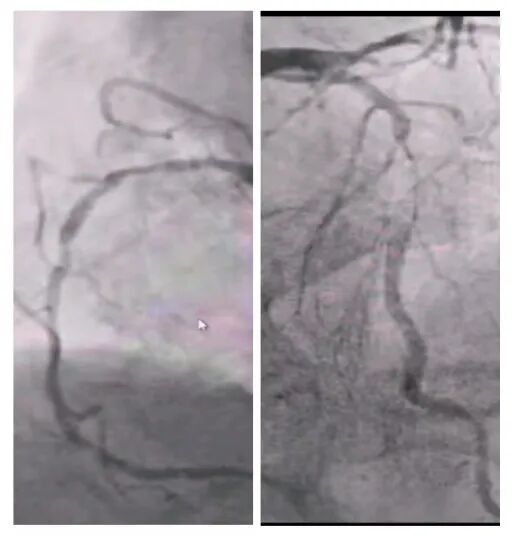

術前冠脈造影

2025年深秋的一個清晨,82歲的馬奶奶(化名)因持續(xù)胸悶氣短被家人送至醫(yī)院心內科。心臟超聲檢查顯示,她的左心房內有一個直徑近5厘米的腫瘤,隨心跳規(guī)律擺動,如同一個隨時可能破裂的“不定時炸彈”。更危急的是,冠脈造影進一步揭示其冠狀動脈多支血管嚴重狹窄,左前降支狹窄達95%,回旋支中段完全閉塞,右冠狀動脈彌漫性病變—兩種致命性心臟疾病的疊加,讓這位高齡患者的生命岌岌可危。

手術當日8時30分,麻醉誘導平穩(wěn)完成。在經食道超聲實時監(jiān)測下,體外循環(huán)管路順利建立,心臟在低溫停跳下顯露術野。主刀醫(yī)生采用“無接觸技術”沿瘤體蒂部完整剝離腫瘤組織,避免碎片脫落;隨后選取左側乳內動脈吻合前降支,大隱靜脈序貫吻合鈍緣支與后降支,完成三支血管重建。125分鐘的轉機時間里,麻醉師全程維持平均動脈壓在65-75mmHg,體外循環(huán)師精準調控流量至2.4L/min/m2。